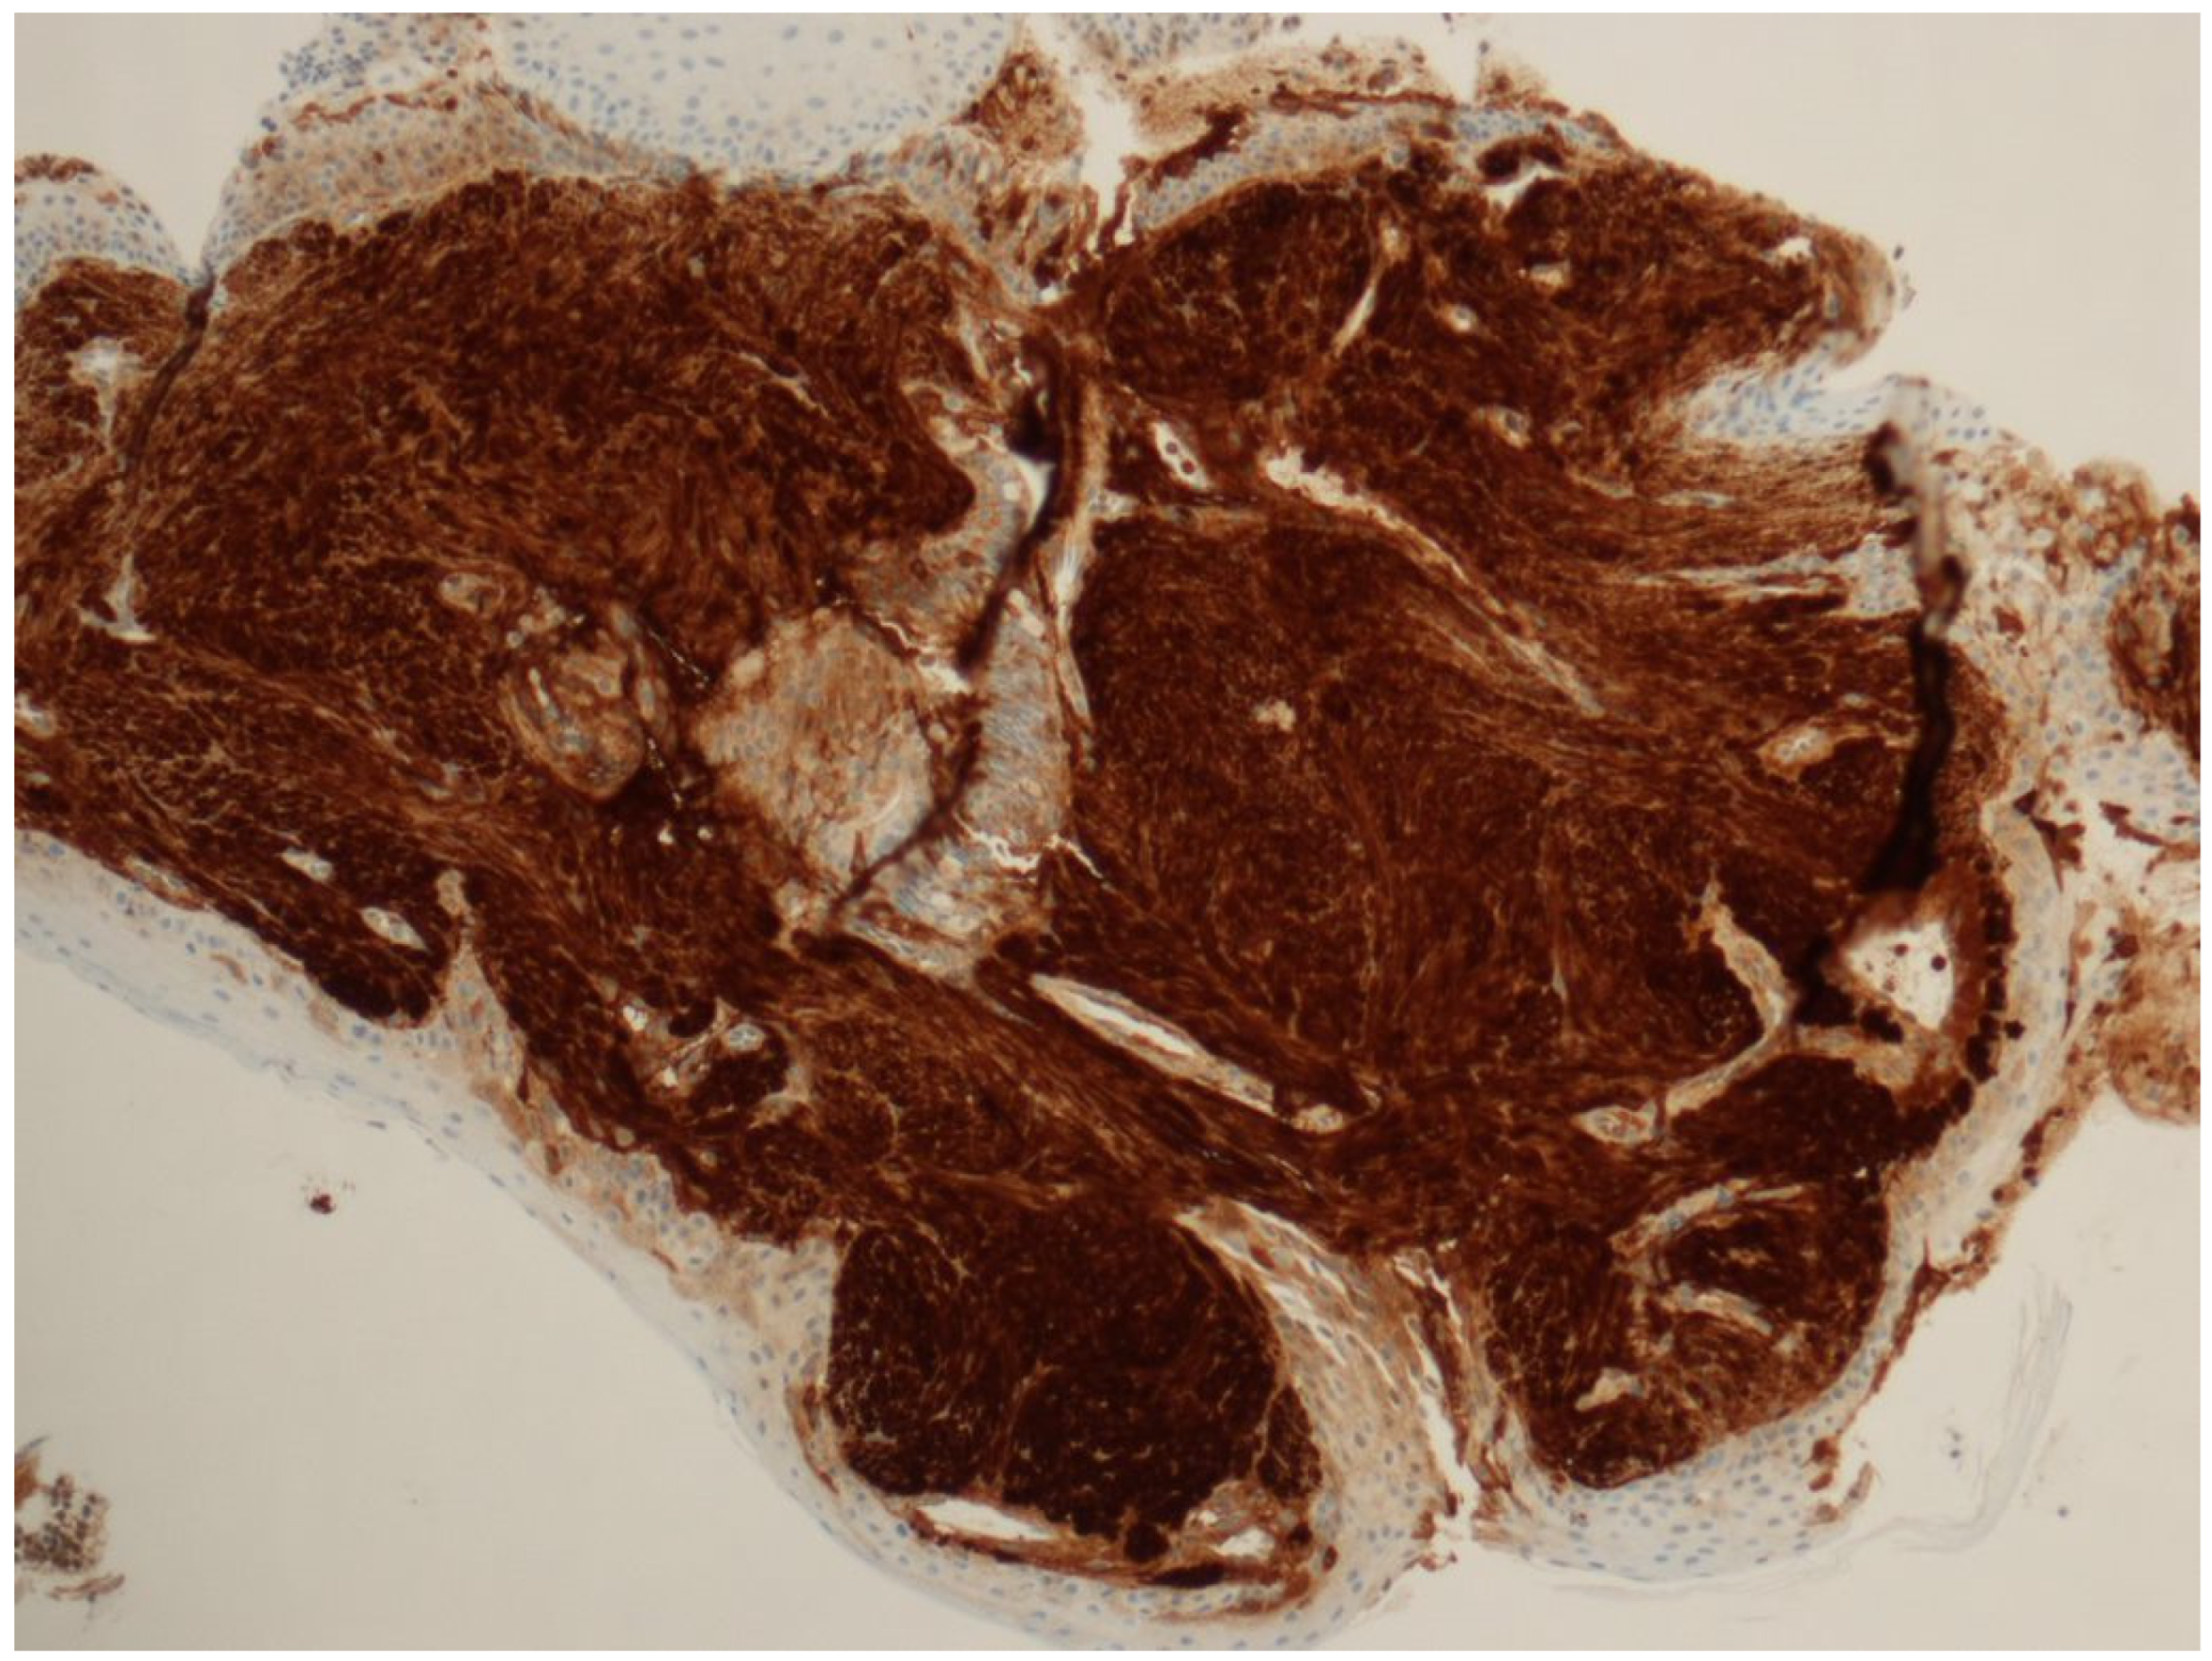

3.2. Pathology Presentation